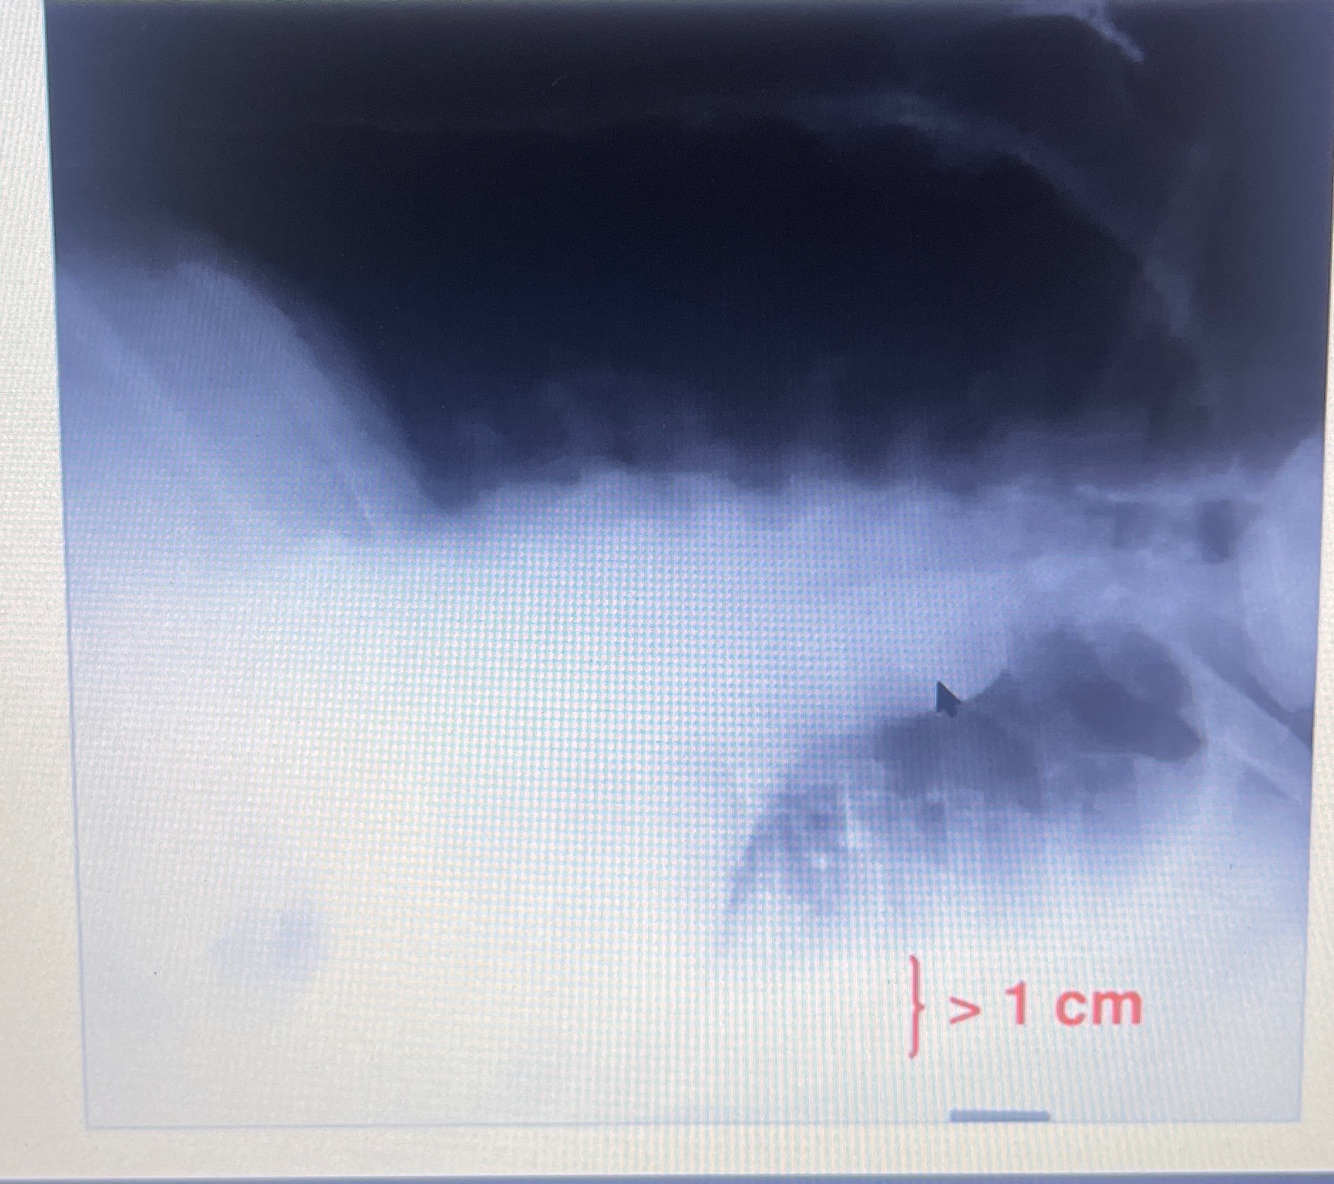

Posso lançar mão da incidência em Laurew ( decúbito lateral com raios horizontais)

Se tiver uma lâmina maior que 1 cm ou 10 mm o derrame é passível de ser puncionado